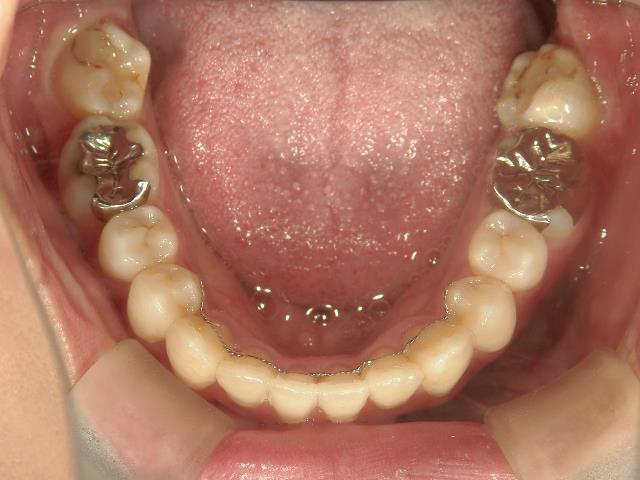

その後、伊藤歯科医院に入社し、やっと矯正をする機会に恵まれました。矯正しているのが目立ちにくい治療を希望し、舌側ワイヤー矯正に挑戦することになりました。

はじめて歯の裏側に器具をつけた時は違和感がとてもあり、特に「さ行」が発音しづらかったのを覚えています。舌が器具に当たりやすいので、傷付きやすく、スペースが狭いため窮屈な感じがしました。

はじめは気になることばかりでしたが、2,3週間するとすっかりと慣れ、しゃべりづらさも改善してきました。それと同時に歯並びも動き始め、月に一回調整をする度に自分で歯の写真を撮って変化を楽しみました。舌側矯正だったので、あまり周囲の人から矯正をしていることを気づかれずに治せたことは嬉しかったです。ずっと悩んでいましたが、矯正をはじめるとあっという間に時間が過ぎていきました。